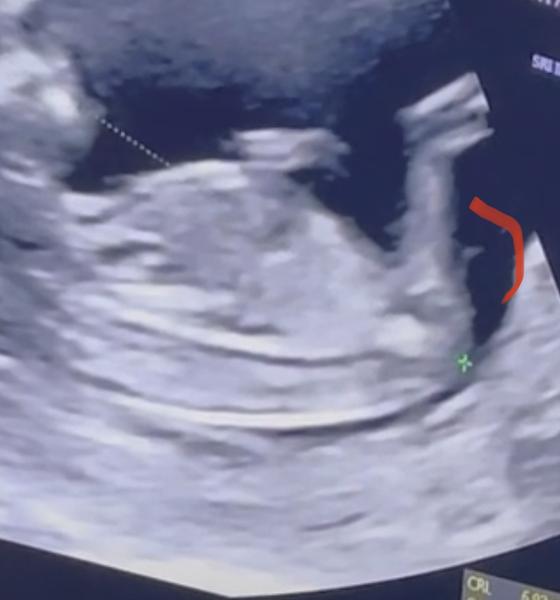

@xkbkbx tady hrbolek bohužel vidět nejde. Možná holka, jestli je hrbolek to co si myslím, ale neupinala bych se na to 😁